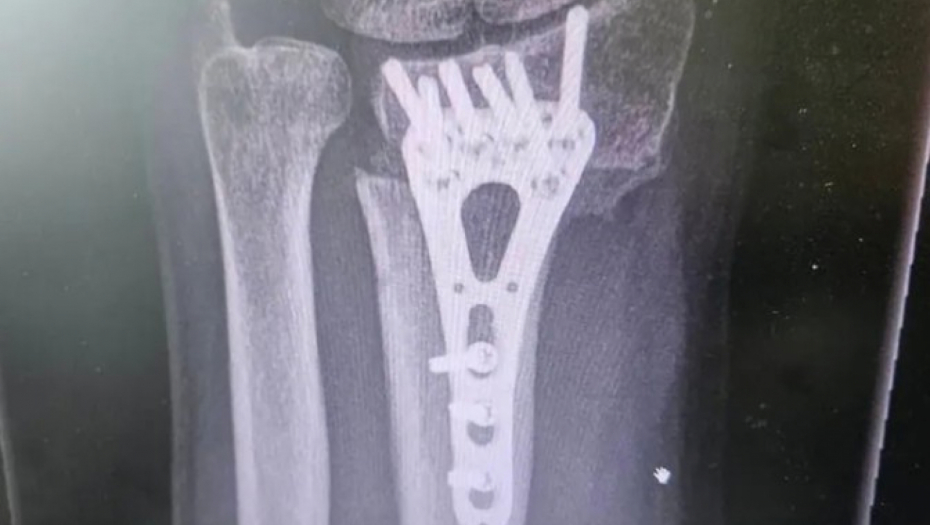

Voditelj Aleksandar Stanković otkrio je da je hitno operisan nakon što je zadobio povredu.

Na svom Instagram profilu je objavio fotografiju preloma ruke do kog je došlo pre tri meseca, te pokazao kako je tekla faza oporavka.

- Ovako je to izgledalo pre tri meseca, a danas je sve u redu. Slomio sam ruku i operisali su me u Opštoj bolnici Sisak. Ruka je zarasla i hvala im što su svoj posao odradili profesionalno i s ljubavlju! - istakao je voditelj.